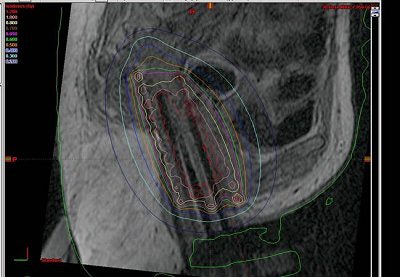

| No inadvertent insertion of interstitial catheter into bladder or rectum noted on CT (below) after MR (above). |

The patients' legs were then brought down and they were reimaged for the CT simulation. "We learned that it was very important to image with the legs down. There was substantial movement with the legs down. But once we figured that out, we were able to perfectly reconstruct the images so that the catheters lined up on MR," Viswanathan said.

The results showed that protection of the bladder and rectum was achieved. In all 10 cases, there was no inadvertent insertion.